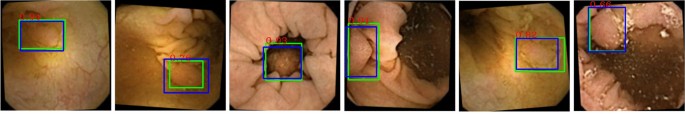

Image acquisition and training

The videos featuring at least one colorectal polyp of any size or morphology were analyzed frame-by-frame, which resulted in an original database of 764 distinct images of polyps. These 764 images were retrieved from 549 distinct polyps, as some of these polyps were reported as a sequence of images when the camera pill approached the polyp. The population under study was FIT positive, and approximately 75% of the polyps were neoplastic. The number of cancerous polyps was below 5%. To maintain a class balance, we further included 764 images of the normal mucous layer, where no significant pathology were detected. To regularize the network, reduce overfitting, ensure that it is rotation and translation invariant, and help remedy the scarcity of data (i.e., to increase the effective size of our dataset), we augmented the database of original images tenfold, using random rotation, scaling, translation, flipping and cropping. We also performed random mirroring at training time. The augmented images containing polyps were all checked for contents, ensuring that polyps were not mistakenly cropped out. These augmentations are justified since masses have no inherent orientation and their diagnosis is invariant to these transformations. Using data augmentation, we created a database containing 15280 images with different grades of colon cleanliness, of which half of them contained colorectal polyps of various sizes and morphology. We then split the images randomly by patient into training, validation and testing sets (80%, 10% and 10% of the full dataset, respectively), constraining the validation and test sets to be balanced. Training, validation and testing of DNN’s performance were carried out in TensorFlow, using a batch size of 20, with the training step size of \(1e-3\). In addition, the NMS threshold \(S_t\) was set to 0.65. A set of examples demonstrating the performance of the trained DNN is presented in Fig. 4, where blue boxes indicate the ground truth annotated manually by the specialist, and green boxes are the output of our DNN. Red numbers above each green box is DNN’s confidence value (range [0, 1]), in which larger numbers are an indication of network’s confidence in regions featuring important findings. The overall performance of our DNN for detection of colorectal polyps within the test set reached a precision of \(AP_{25}=99.5\%\) and \(AP_{50}=95.8\%\), \(AP_n\) referring to the average precision calculated using the intersection over union (IoU) criterion.